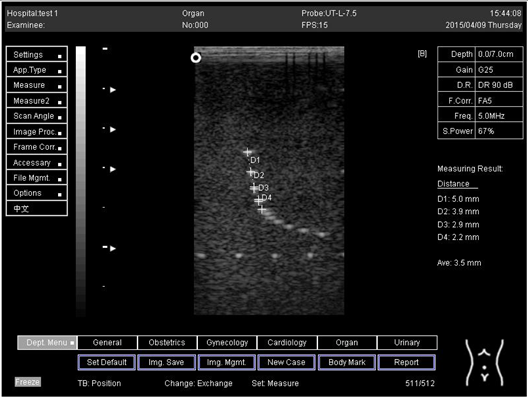

9.0 Axial resolution

Biomimetics 07 00130 i001

D1 = 4.9

D2 = 4.1

D3 = 3.1

D4 = 2.2

Lateral resolution

Biomimetics 07 00130 i002

D1 = 5.0

D2 = 4.0

D3 = 3.0